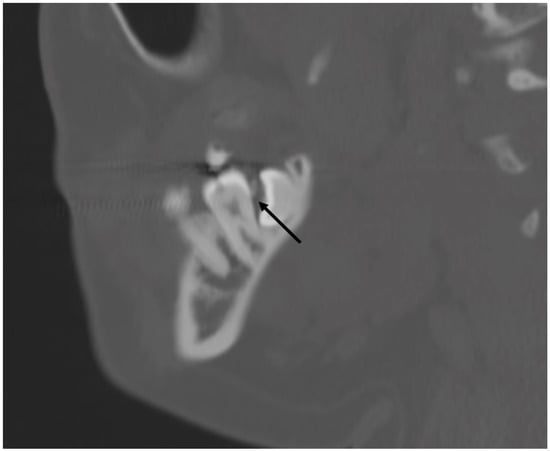

3.5.2. Dental Decay Radiologic Correlations

3.5.4. Periodontal Disease Radiologic Correlations